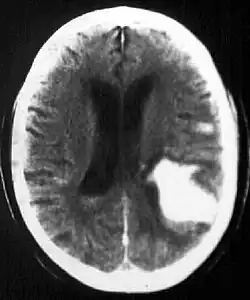

Computed tomography (CT scan): A CT scan may be normal if it is done soon after the onset of symptoms. A CT scan is the best test to look for bleeding in or around your brain. In some hospitals, a perfusion CT scan may be done to see where the blood is flowing and not flowing in your brain.